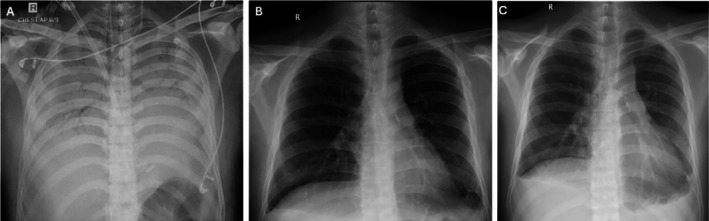

Paraquat, a commonly available herbicide, when consumed in high doses, affects organs with high blood flow (lungs, heart, kidney and liver), leading to pulmonary fibrosis, respiratory failure and death. Few reports of rescue lung transplantation exist. Complete depletion of paraquat from the body is necessary prior to transplant; however, timing for and concerns after lung transplantation remain unknown. We report 2 patients (median age 19 years) with severe respiratory failure requiring extracorporeal membrane oxygenation support, acute kidney injury requiring haemodialysis and acute liver injury in the pre-transplant period. Volume of paraquat consumption was more than 30 mL and PF ratio less than 100 before transplant. Once their urine paraquat level was negative (median time 32 days), both underwent bilateral lung transplantation after receiving an induction agent with basiliximab and were continued on triple immunosuppressant following the transplant. With reported mortality rates reaching up to 90%, lung transplantation remains a reasonable option for patients with paraquat poisoning not responding to conventional treatment options. Once paraquat levels are negative and after optimising renal and liver function, these patients could be considered for bilateral lung transplantation and have successful outcomes as reported here.